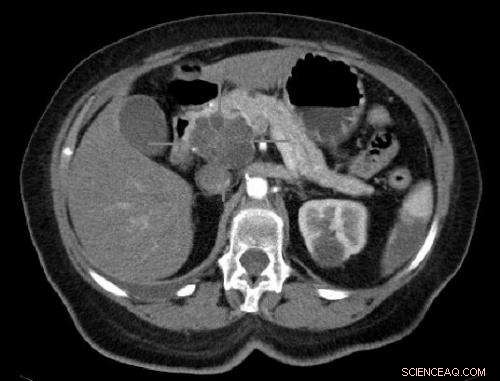

Axial CT image with i.v. contrast. Macrocystic adenocarcinoma of the pancreatic head. Credit: public domain

What makes pancreatic tumor hard to cure is the dense stromal barriers sheltering cancerous cells. The penetration of drugs is hindered. To promote the infiltration of therapeutics, an adjuvant is used prior to gemcitabine to remodel the stroma. Nevertheless, this widely studied strategy may raise the risk of tumor metastasis and tumor cells' resistance to drugs.

In this study, the researchers used an acid-sensitive, membrane-disruptive micelle (M-14K) as the model for such nanoparticles.

This long-circulating nanoparticle showed acid-activated cytotoxicity indiscriminately to both cancerous and fibroblast cells, which is realized by acid-activatable disruption of cellular membrane integrity. The ability of such nanoparticles to penetrate the stromal barrier and eliminate the sheltered cancer cells was verified both in vitro using three-dimensional (3D) cell spheroids and in vivo using mouse models bearing BxPC-3 tumors.